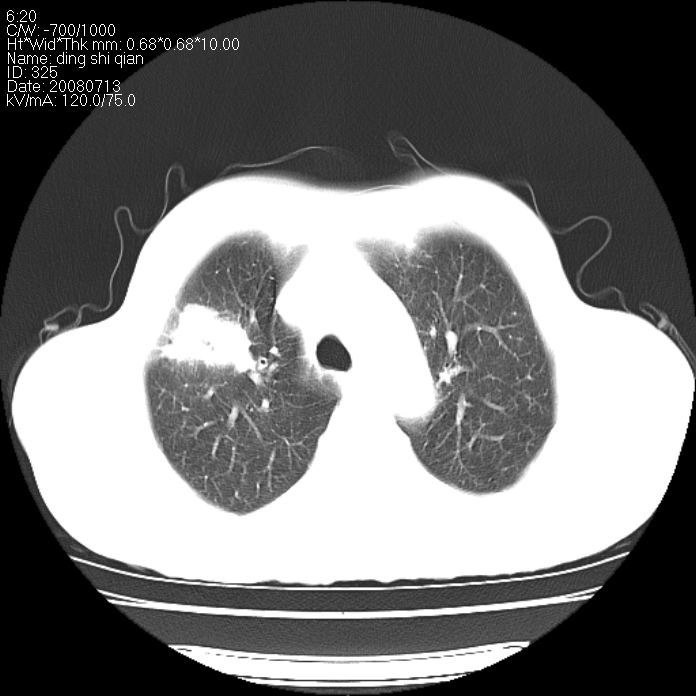

标题: CT14654:男 50岁 近来胸痛 [打印本页]

标题: CT14654:男 50岁 近来胸痛

右侧上肺块状软组织影,浅分叶,边缘毛刺证,与胸膜粘连,考虑:周围性肺癌

右肺上叶周围型肺癌可能性大。

右侧上肺块状软组织影,浅分叶,边缘毛刺证,与胸膜粘连,考虑:周围性肺癌!支持!

典型右肺周围型肺癌

首先考虑周围性肺癌,建议强化或穿刺明确

考虑: 右肺上叶周围型肺癌可能性大.

右肺上叶周围型肺癌。